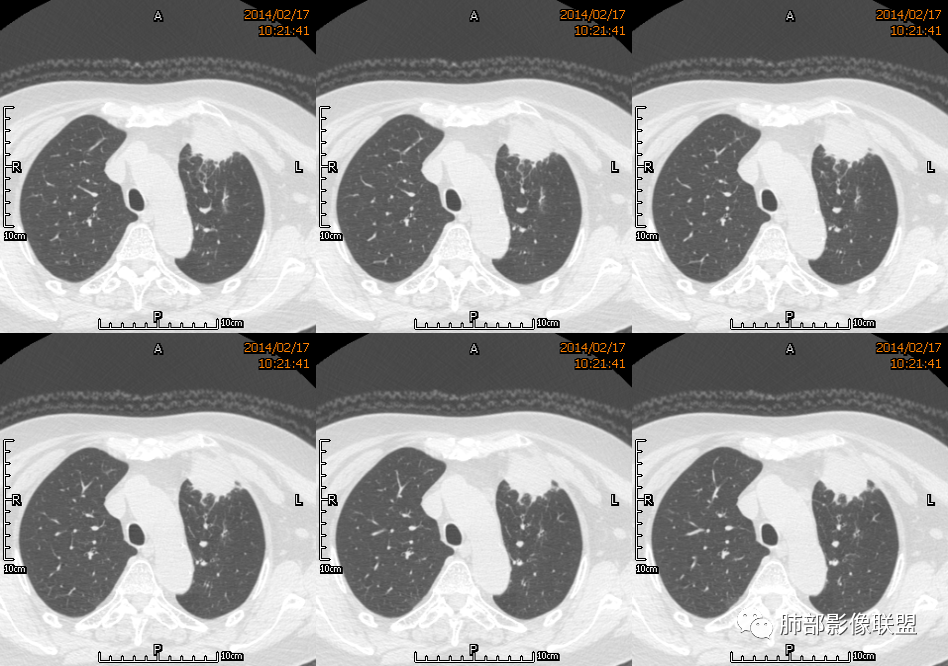

2.左肺上叶前段胸膜下块状影,不规则呈“逗点样”延向肺门区,边界清楚,未见分叶、毛刺及张力,表面不规则棘突,状如“火焰”或“日冕”。相邻胸膜增厚,未见栽赃、卫星病灶。

4.肺门纵隔未见肿大淋巴结。